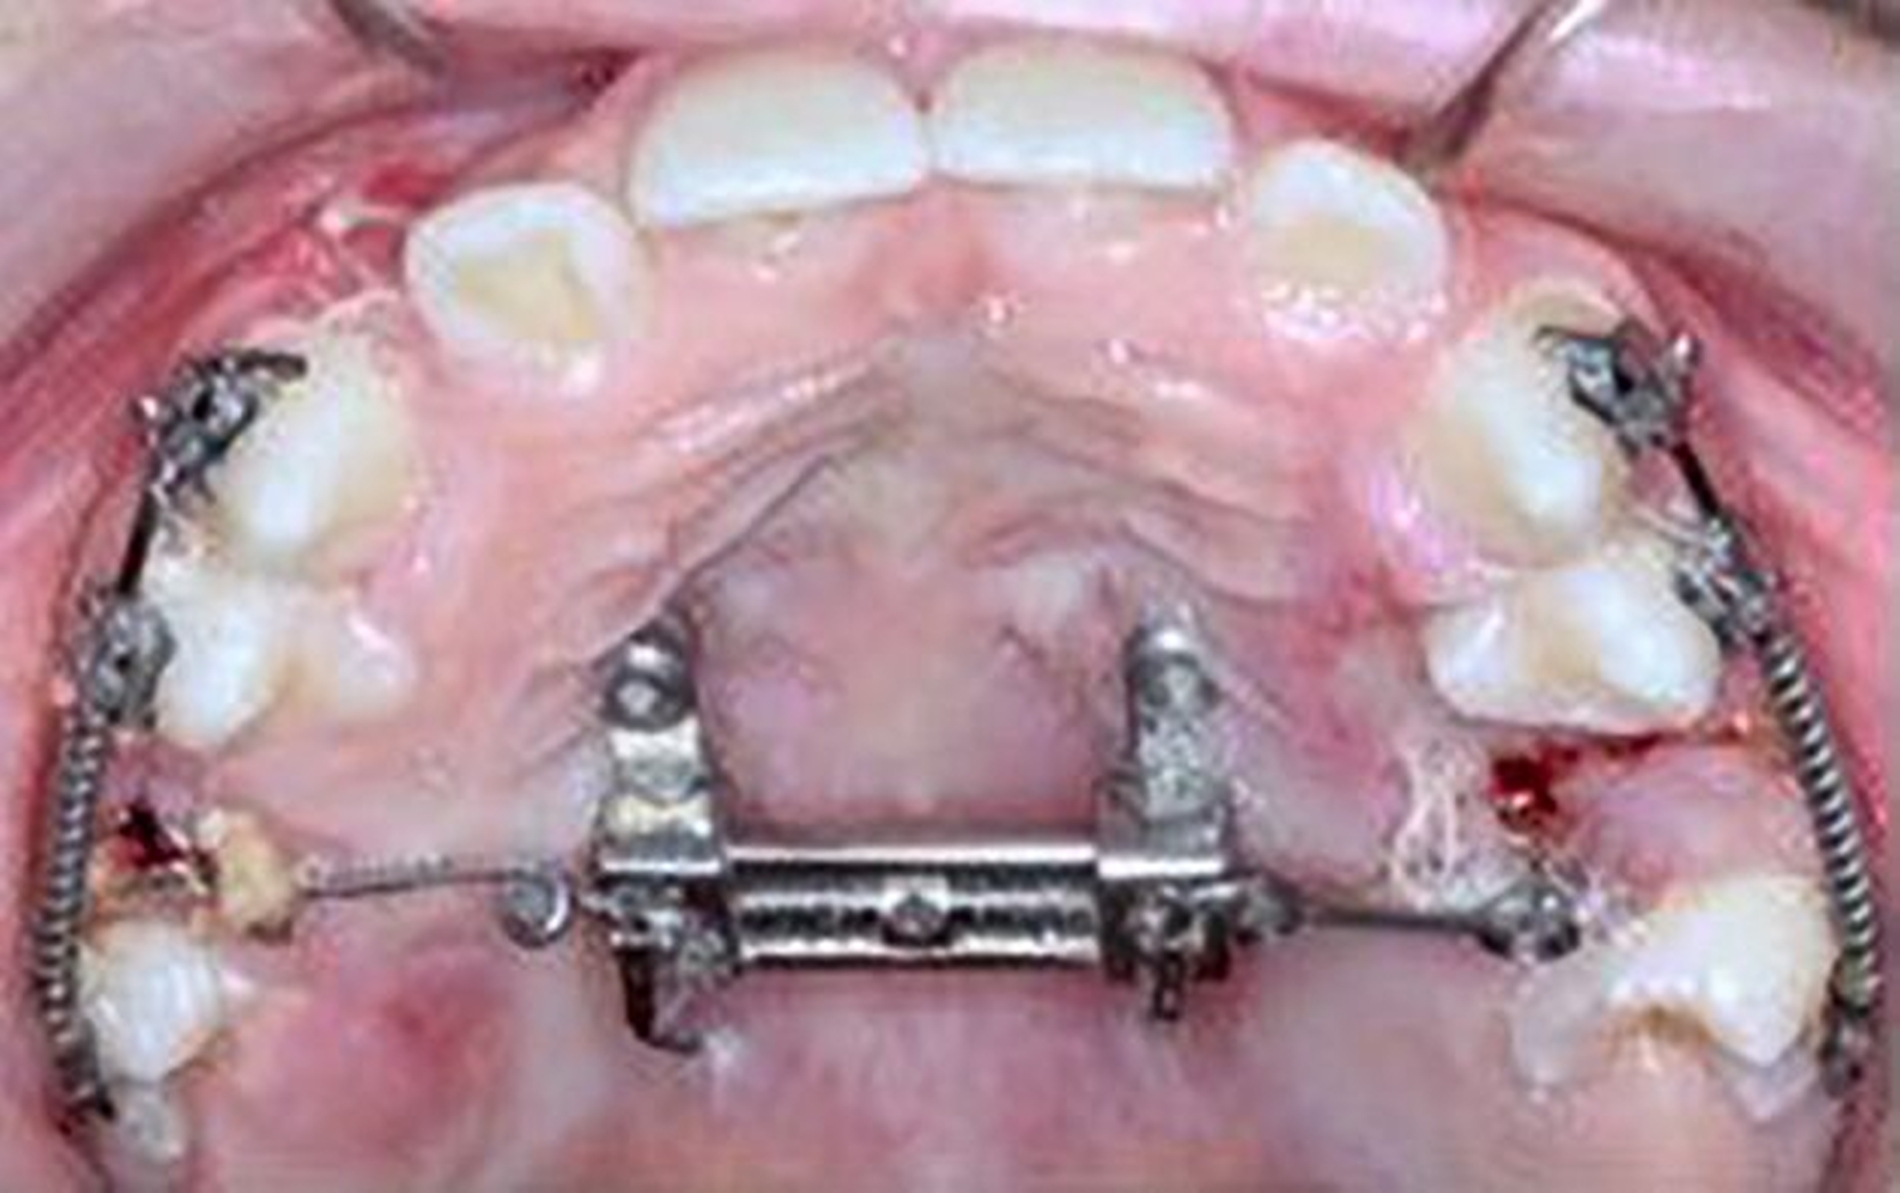

Die Zähne 36, 37, 46 und 47 wurden in Allgemeinanästhesie chirurgisch freigelegt. Zusätzlich wurden die beiden paramedianen Mini-Implantate (2 x 9 mm, Benefit System; PSM North America, Indio, CA) ohne Vorbohren mithilfe der zuvor hergestellten Schablone inseriert (Abbildung 3). Für die Platzierung der Mini-Implantate wurde ein Winkelschraubendreher verwendet. Direkt nach der Operation wurde die bmx DIRECT Hyrax-Schraube (10 mm, BENEfit®-System, Dentalline, Birkenfeld, Deutschland) an den Mini-Implantaten befestigt, um ein MARPE zu erzielen (Abbildung 4).

Die Eltern des Patienten wurden angewiesen, die Schraube einmal täglich zu aktivieren. Die gesamte Aktivierungszeit der Hyrax-Schraube betrug circa zehn Wochen. Während dieser Zeit vergrößerte sich die transversale Dimension des Oberkiefers um sieben Millimeter im posterioren Bereich (Milchmolaren) und um fünf Millimeter im anterioren Bereich (Milcheckzähne). Währenddessen trat ein mediales Diastema auf (Abbildungen 4b und 4c), das auf eine skelettale transversale Expansion des Oberkieferknochens hinwies. Nach der aktiven Expansionsphase der Hyrax-Apparatur wurde das Gerät für weitere Behandlungszwecke verwendet: Erstens als Retentionsgerät, um die bereits erzielte transversale Oberkieferbreite zu halten und zweitens als skelettal verankerte Apparatur zum Einstellen der retinierten und verlagerten Zähne mithilfe individuell angefertigter Kragarme. Hierfür wurde die Hyrax-Apparatur im zahntechnischen Labor modifiziert, indem Kreuzröhrchen für eine stationäre Befestigungen für die Drähte des Kragarms angebracht wurden.